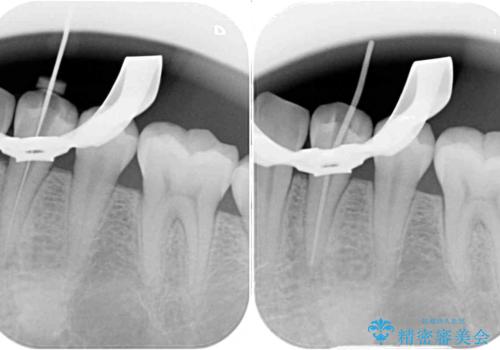

レントゲン写真などで診査を行ったところ、左下の第一小臼歯の神経組織が壊死し、根尖部周辺の骨に炎症が認められました。

まずは根管治療を行い、症状が消退したことを確認してオールセラミッククラウンにて補綴治療を行うこととしました。

根管治療後6ヶ月でレントゲン写真を撮影したところ、根尖部周辺の炎症が消退していることが認められました。